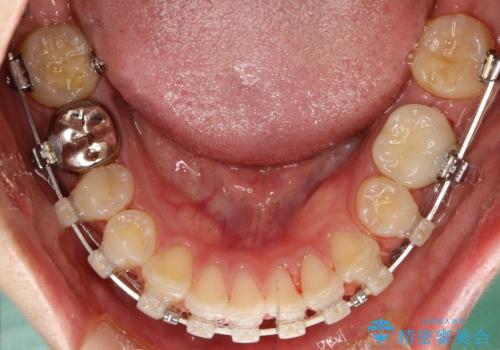

出っ歯の矯正 抜歯をしてしっかり引っ込めるワイヤー矯正

- 矯正装置

- 審美装置

- 治療計画

- 出っ歯を気にして来院されました。

しっかり前歯を下げるために抜歯を合計3本行いワイヤーにて矯正を行う計画としました。